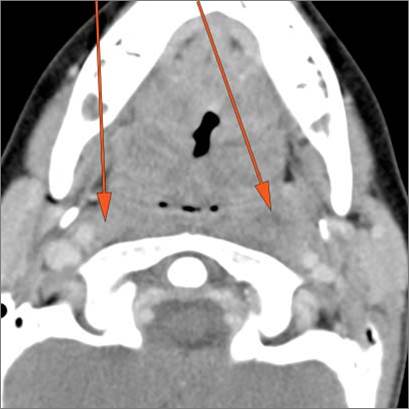

Cervical Lymph Nodes

There is reactive cervical lymphadenopathy. [Yes/No]

There is suppurative cervical lymphadenopathy. [Yes/No]